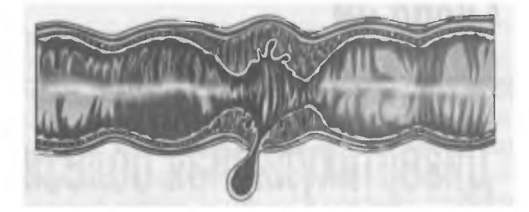

Различают три типа

морфофункциональных изменений, выявляемых рентгенологически при дивертикулярной

болезни.

Первый тип - просвет кишки

3,5-4,0 см, гипертонус не выражен, межгаустральные складки сглажены,

эластичность стенки сохранена.

Второй тип - просвет 2,5-3,5

см, гаустральный рисунок деформирован, высокие межгаустральные складки,

эластичность сохранена.

Третий тип - просвет менее 2,5

см, стойкий гипертонус, гаустрация хаотичная, пилообразный контур, эластичность

снижена, кишка фиксирована.

Третий тип морфофункциональных

изменений является наименее благоприятным в прогностическом отношении, при нем

следует ожидать таких осложнений заболевания, как дивертикулит, паракишечный

инфильтрат, абсцедирование или перфорация.